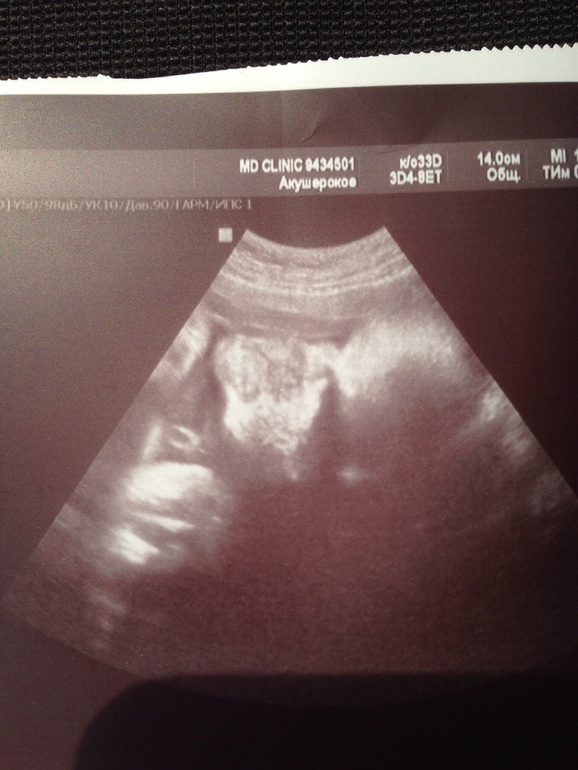

А это наши щечки, точнее одна щека.